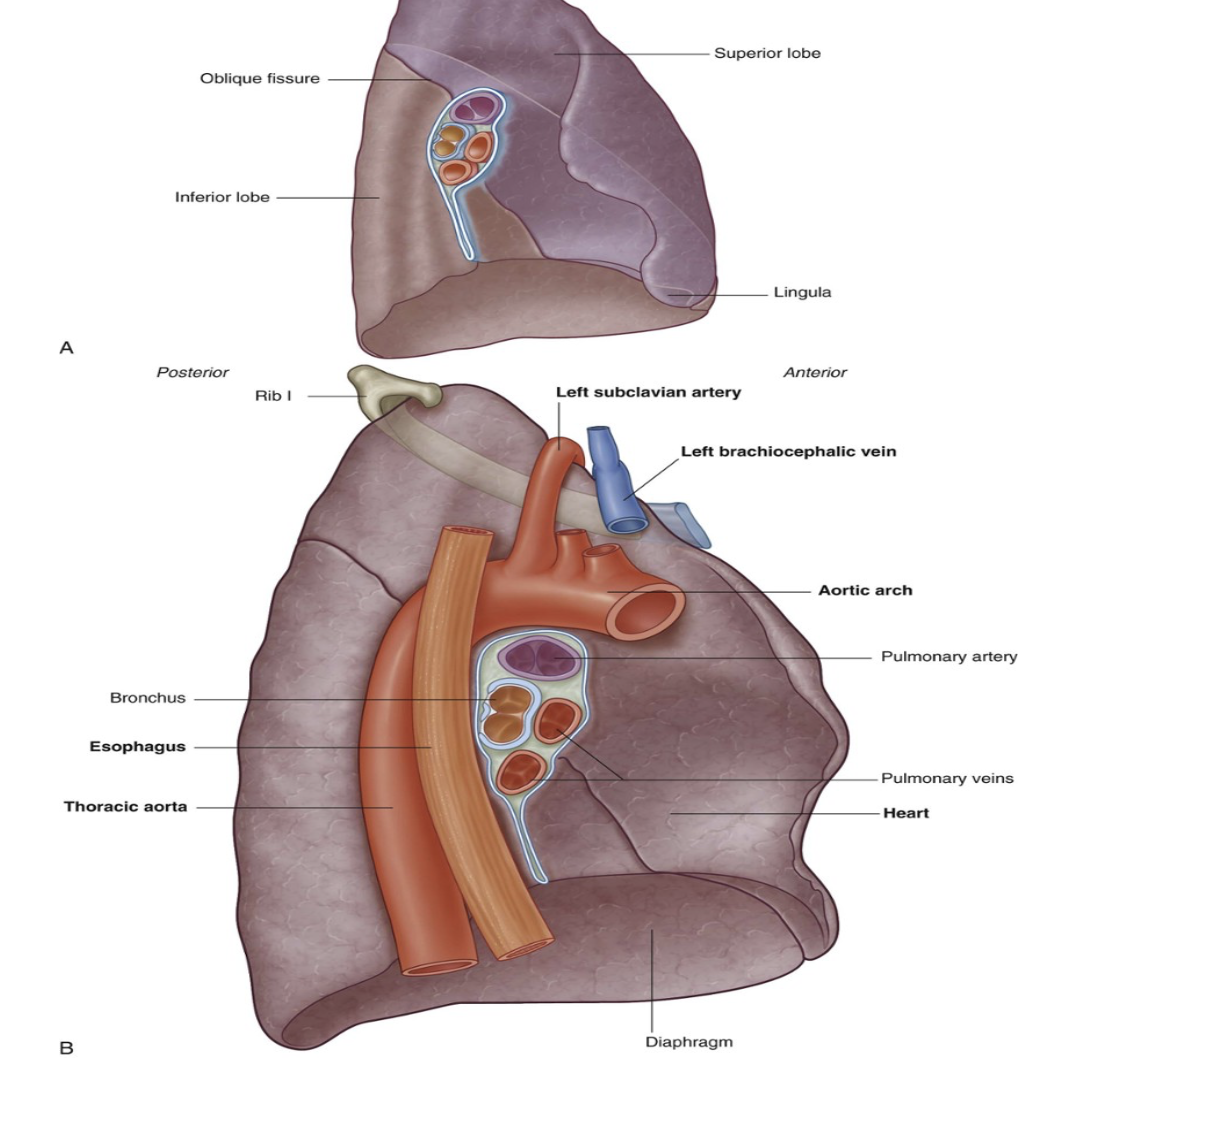

Left lung lobes & fissure

2 — superior & inferior, with fissure separating them

Superior lobe —

In contact with upper part of anterolateral wall & apex of this lobe projects into the root of the neck contact

Costal surface of inferior lobe — in contact with posterior & inferior walls

Oblique fissure —

Separates superior & inferior lobe — slightly more oblique than that on right lung

Left lung is slightly smaller than right lung due to heart on left side (thus left lung has corresponding cardiac notch & additionally the associated lingula of the left lung which projects over the heart bulge

Important structures in the mediastinum & root of neck that are adjacent to medial surface of left lung

Heart

Aortic arch,

Thoracic aorta

Esophagus

Note about subclavian vessels & left lung

The left subclavian artery and vein arch over and are related to the superior lobe of the left lung as they pass over the dome of the cervical pleura and into the axilla